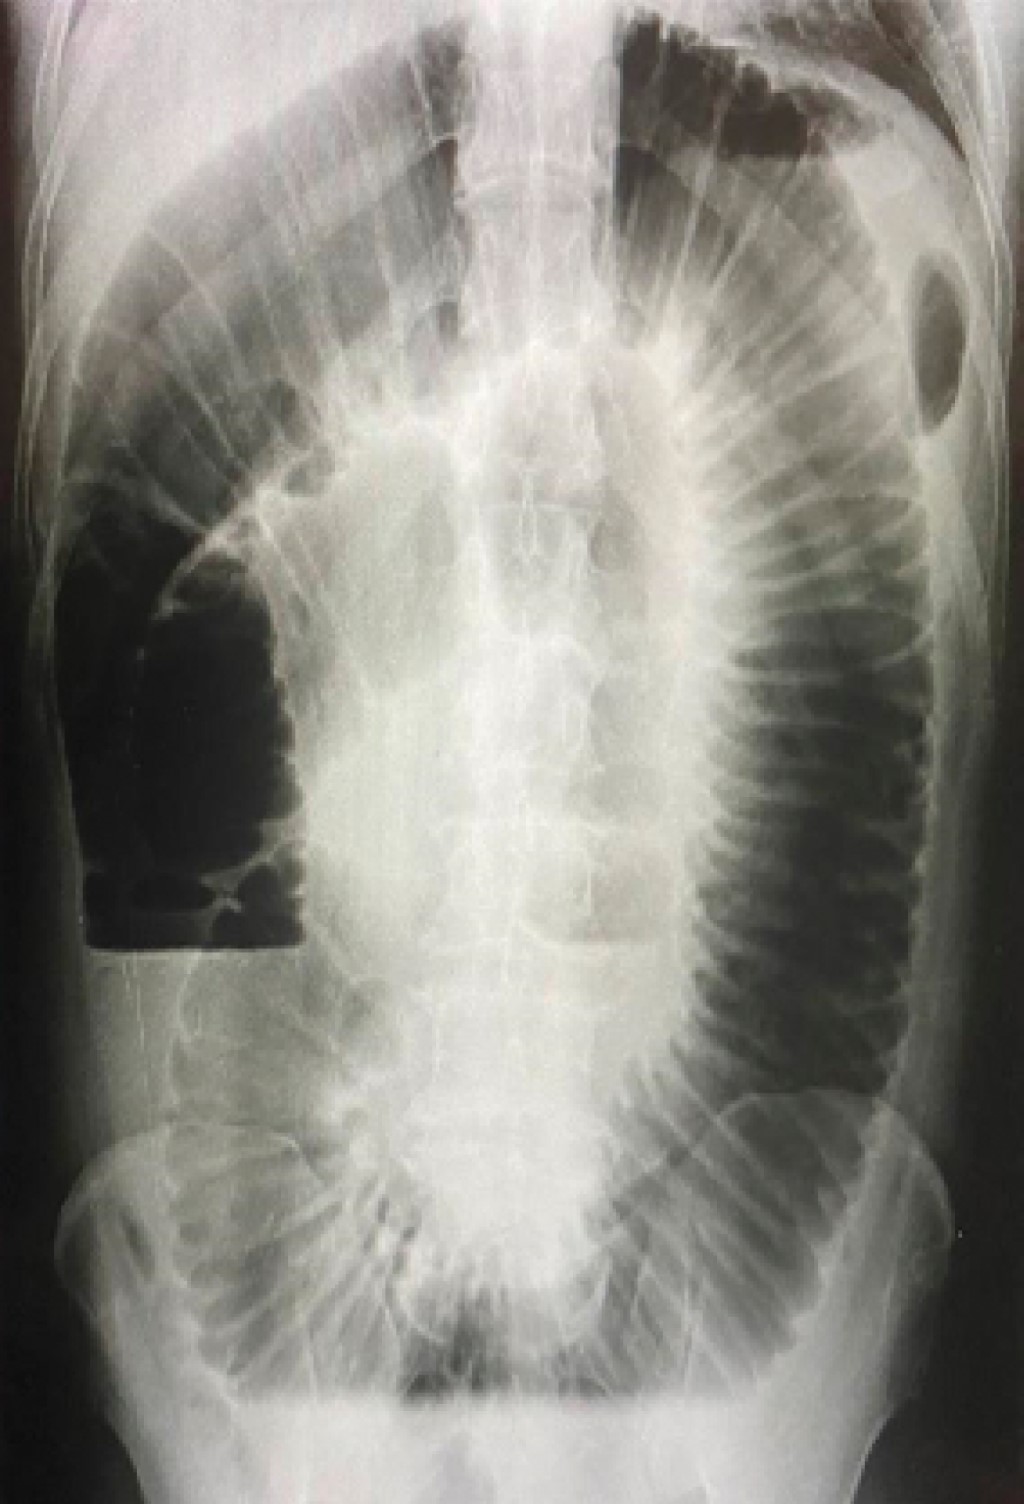

Laboratory findings are shown in Tables 2, 3 and 4. Plain abdominal radiography in the standing position showed the presence of slight bowel distention, inter loop edema with a coin stack image, and hydro-aerial levels without air in the colon (Figure 1). Simple abdominal radiography in the supine position showed a coin stacking and a duodenal bubble image (Figure 2).

Figure 1